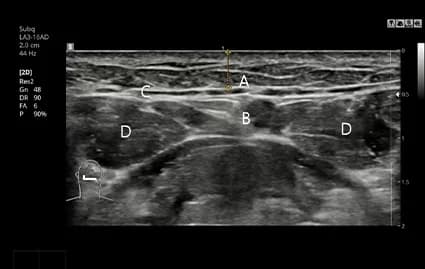

手術前 CTおよび超音波撮影

CT撮影および超音波検診で唾液腺の位置と大きさを精密に分析し、必要に応じて繊細なオーダーメイド唾液腺除去手術を進行